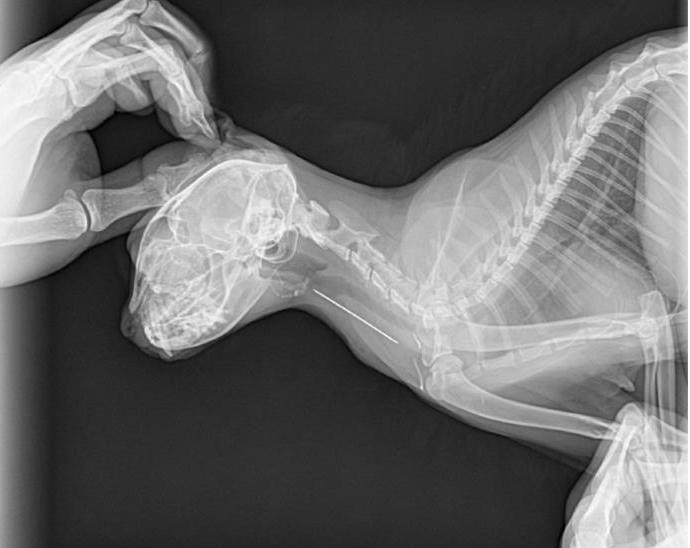

由于猫咪贪吃或主人的疏忽,吞食一些无法消化的异物以及食物卡住。不要太过于相信你的猫咪,我见过吞针的猫咪,针从脖子扎出一个洞。吞针的、吞线的、吞塑料袋的~~等

解决办法:异物可大可小,建议立刻就诊检查。